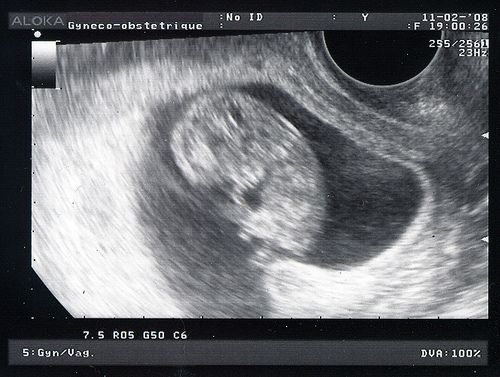

ou 10 sa et 5 jours...

Qu'est ce que tu as grandi! Tu vas bien, ton coeur bat, je l'ai vu, je l'ai entendu. Je t'ai vu bouger et je ne stresse plus. Tu mesures 3,6 cm! On voit bien ton profil, ton coeur en plus foncé sous le menton. Le gynéco a mesuré ta nuque et elle est toute fine, ça limite grandement le risque pour le syndrome de Down. C'est la trisomie, une maladie génétique. Je devrai faire d'autres tests dans une prise de sang pour m'assurer que tu n'auras pas cette maladie très grave qui déforme le corps, le visage et qui rend plus lent (un handicap mental brrr). Je suis déjà rassurée par la taille de la nuque. Ces risques augmentent en fonction de l'âge de la mère et des conditions de grossesse. Mais je suis jeune (28 ans, ça va non?), je ne bois pas, je ne fume pas, je ne me drogue pas. Je reste confiante. Je ferai la prise de sang assez vite.